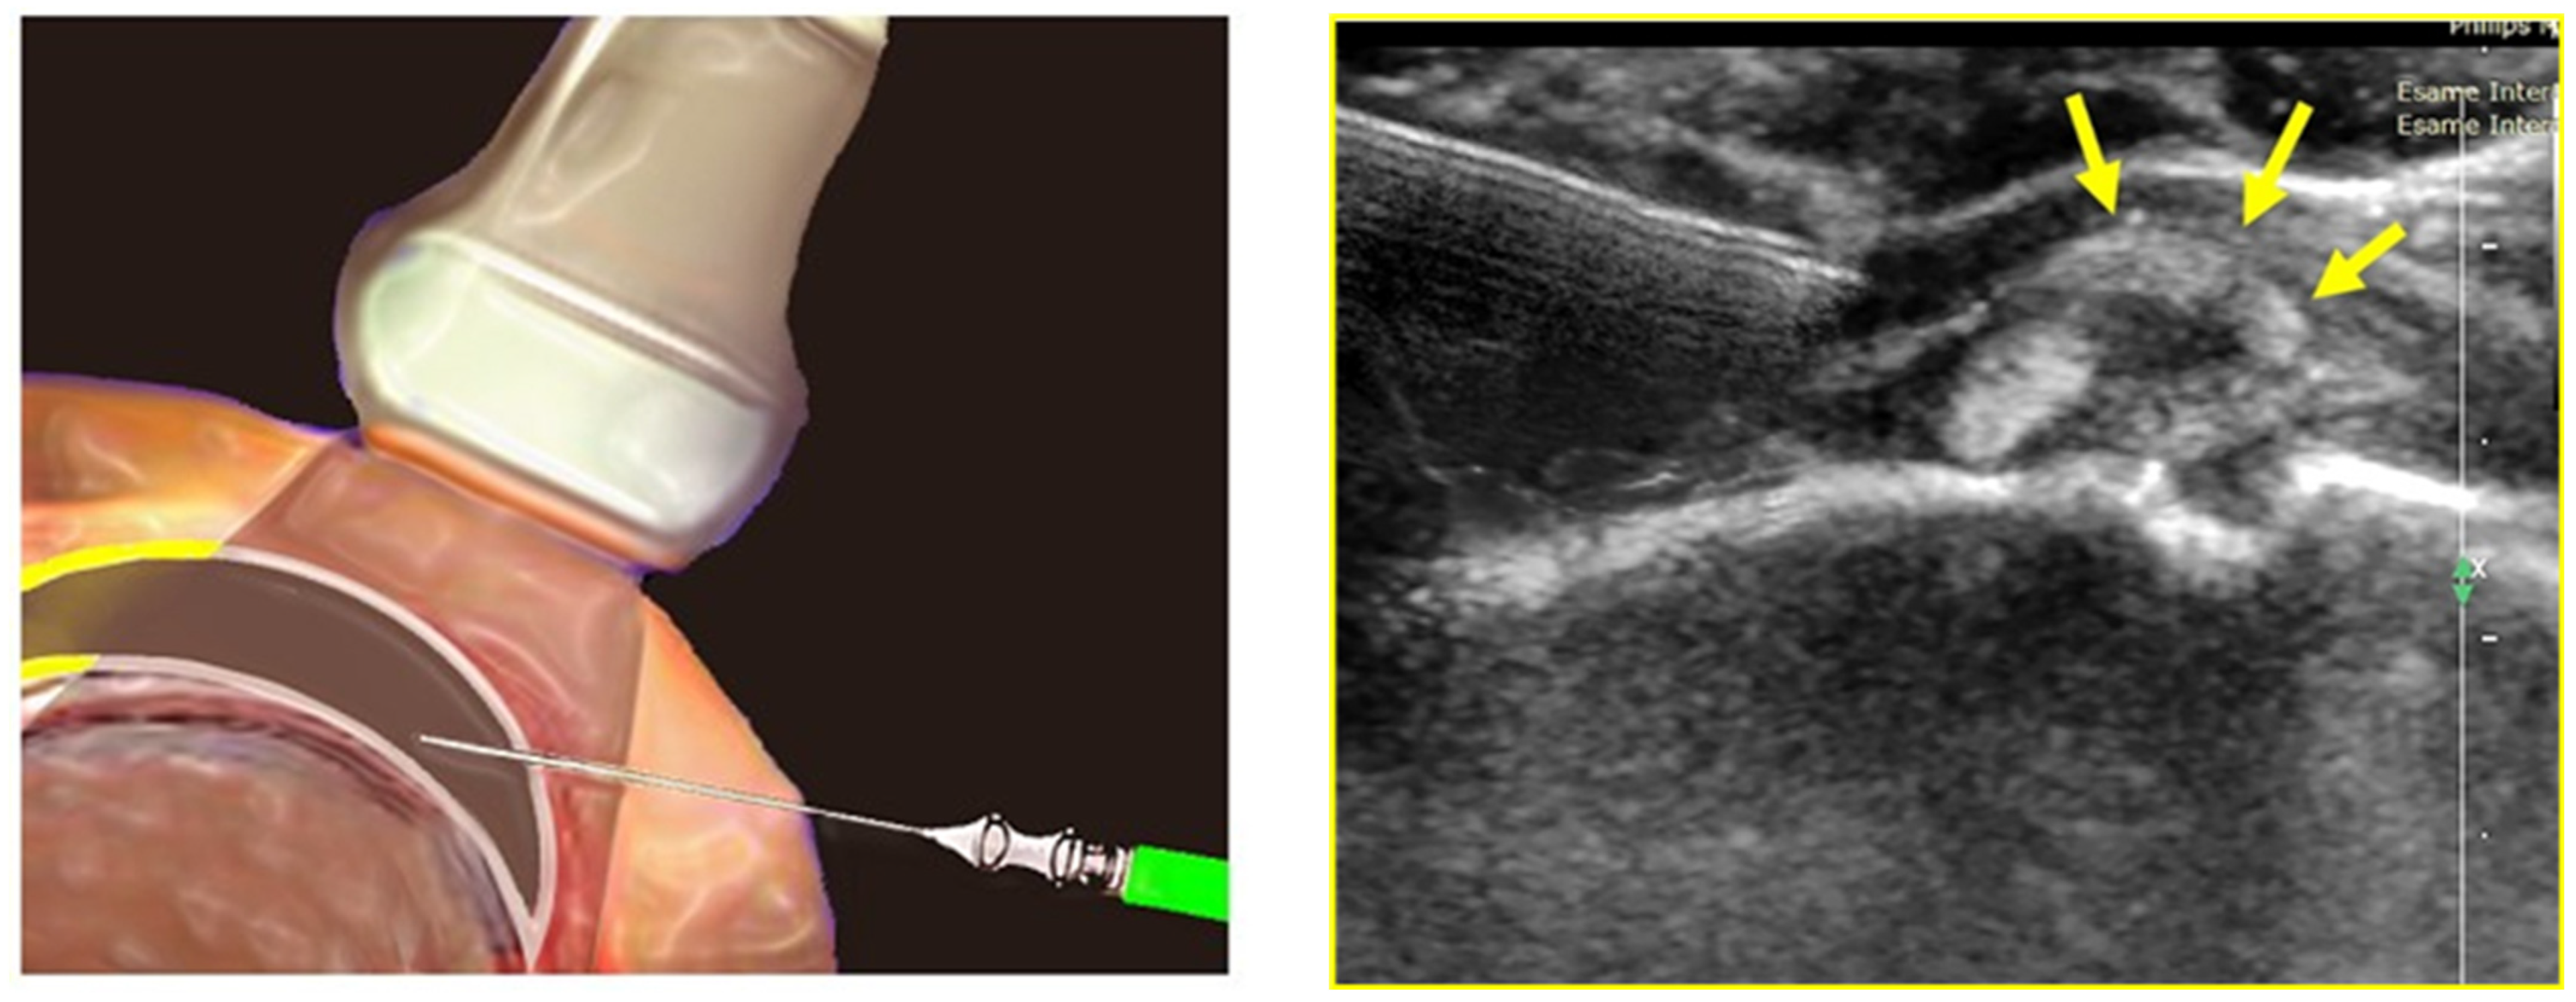

2.5. Ultrasound-Guided Infiltrative Treatment

- Ricci, V.; Chang, K.V.; Özçakar, L. Ultrasound-Guided Hydrodilatation of the Shoulder Capsule at the Rotator Interval: Technical Tips and Tricks. Pain. Pract. 2020, 20, 948–949. [Google Scholar] [CrossRef]

- Elnady, B.; Rageh, E.M.; Hussein, M.S.; Abu-Zaid, M.H.; El-Sayed Desouky, D.; Ekhouly, T.; Rasker, J.J. In shoulder adhesive capsulitis, ultrasound-guided anterior hydrodilatation in rotator interval is more effective than posterior approach: A randomized controlled study. Clin. Rheumatol. 2020, 39, 3805–3814. [Google Scholar] [CrossRef]